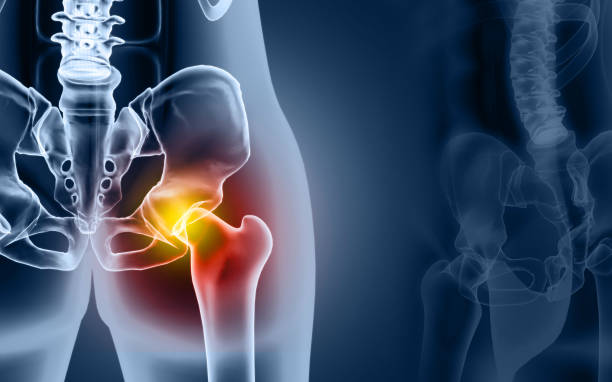

고관절 통증의 일반적인 원인 중 하나는 허리디스크입니다. 허리디스크는 허리 부위의 디스크에 문제가 생겨 발생하며, 이로 인해 통증을 겪게 됩니다. 하지만 모든 고관절 통증이 허리디스크로 연결되지는 않습니다. 고관절 주변에도 다양한 원인이 숨어 있을 수 있습니다.

고관절 통증은 종종 단일 원인뿐만 아니라 복합적인 문제에서 비롯됩니다. 이것이 진단과 치료를 어렵게 만들 수 있습니다. 예를 들어, 허리디스크와 함께 관절 주위의 염증, 근육 문제, 혹은 다른 구조적 문제가 동시에 발생할 수 있습니다.

고관절 통증을 관리하고 치료하기 위해서는 다양한 요인을 고려해야 합니다. 통증을 완화하고 원인을 해결하기 위해 개별 환자에게 맞춤형 치료 계획이 필요합니다. 이때, 관절과 근육의 조화로운 기능을 회복시키기 위한 재활운동이 중요합니다.